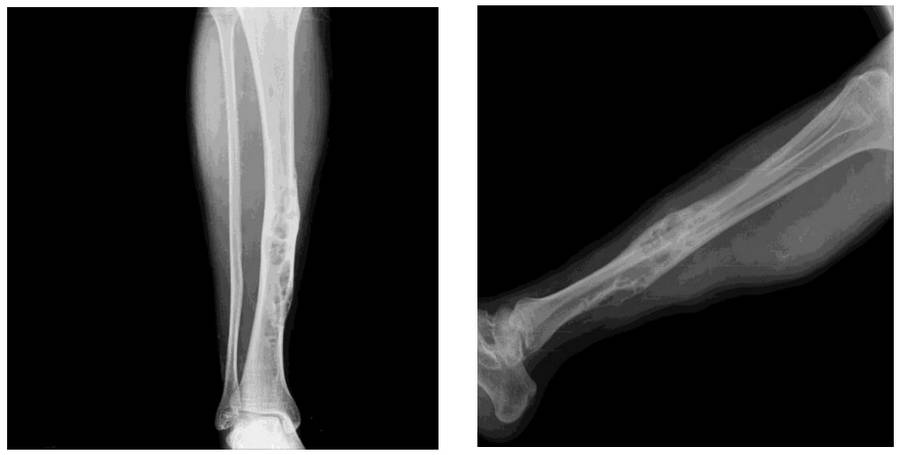

Ameliyat Öncesi: Röntgende tibia orta hatta düzensizlilk ve şekil bozukluğunun eşlik ettiği heterojen kitle dokusu görülmekte